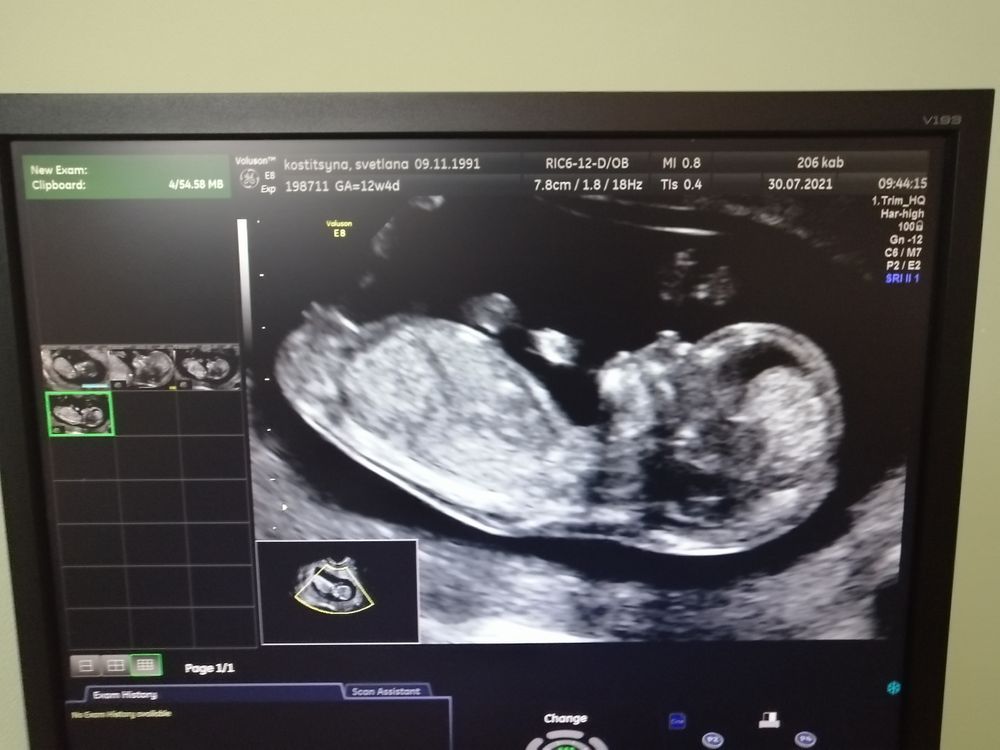

Мои ровно 12 недель (по 1 скринингу)-третья беременность

Изображение

Уж как то мне повезло что-ли 😄, но все мои беременности не богаты на большие животы. По 1 скринингу и по пдм срок различается почти в неделю - сегодня ровно 12 по 1 скрину.